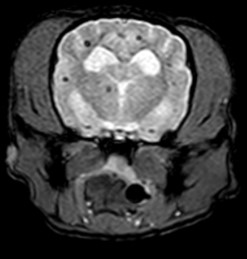

MRI의 경우 특히 뇌와 척수의 신경계와 같은 연부조직의 영상화에 특화되어 있어 다른 영상 기법보다 뛰어난 해상도를 나타냅니다.

- 뇌수두증

- 뇌종양

- 뇌수막염

- 두경접합부 질환

뇌수두중 -

후두골이형성,키아리 기형 -

척수공동증 -

AAI